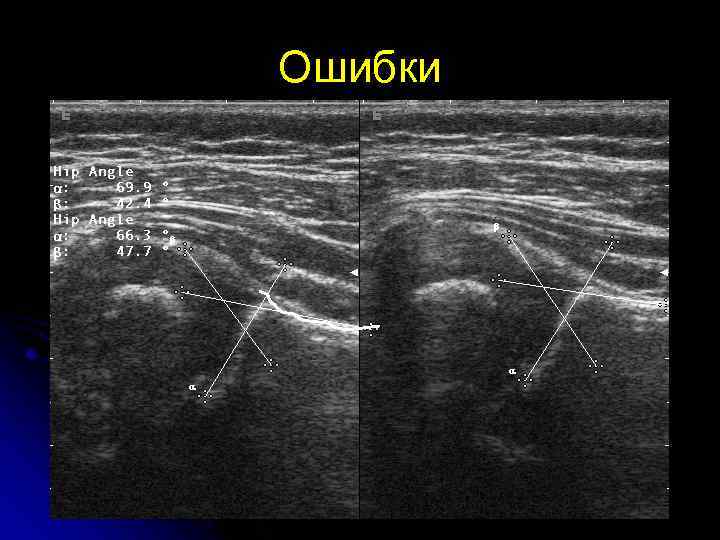

Ошибки